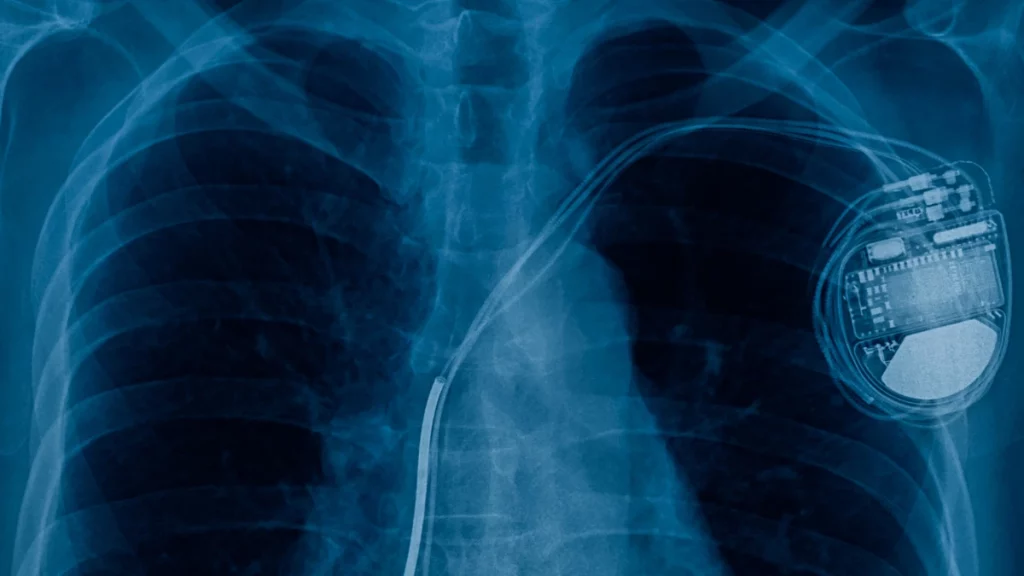

Como os demais dispositivos cardíacos eletrônicos implantáveis (DCEI), ele funciona por meio de impulsos elétricos que, neste cenário, servem para estabilizar as batidas e o processo geral.